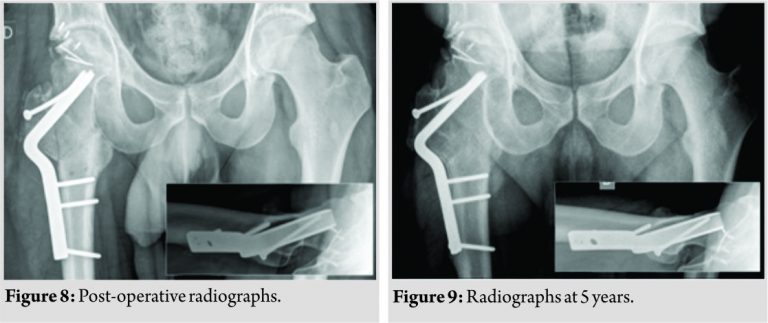

After head reduction, the intertrochanteric osteotomy was stabilized with a 120° blade plate (Depuy Synthes; 4528 Zuchwil Switzerland) and the trochanteric osteotomy with additional 4.5 mm lag screws (Fig. 8). For the first 3 post-operative months, the patient was mobilized on crutches with partial weight-bearing and active assisted mobilization of the hip in a lateral position under supervision by a physiotherapist. Radiographically, all osteotomies and fractures had united at 3 months, and the patient progressively started full weight-bearing and normal daily activities. At 5 months he was back to initial work as a truck driver. Asymptomatic, heterotopic ossification around the femoral head (Brooker Grade I) was seen. All his daily and recreational activities (Ski and Squash) could be restarted without any limitations. Satisfaction with the treatment was reported from the patient since the beginning. The hip mobility became a normal range after 6 months. At his most recent follow-up visit, 5 years after injury, the patient was very satisfied and completely asymptomatic. He had a symmetric range of motion of his hips and no limitations in daily and recreational activities. Radiographs demonstrated union of all osteotomies; osseous integration and remodeling of the bone graft as well as correct congruity and containment of the hip joint, without signs of osteoarthritis (Fig. 9, 10, 11). He was able to work 100% in his original profession. The Harris hip score was 98 points.